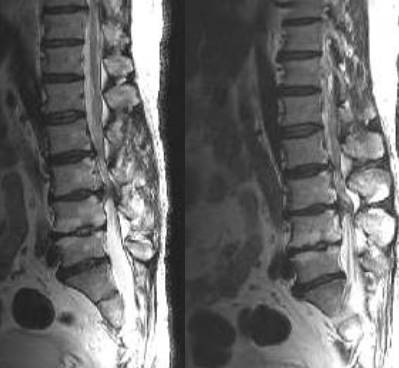

5、MRI检查:此检查能进行横断面、矢状面、斜切面的扫描。软组织显示好,尤其对髓内病变诊断率高。

椎管狭窄硬膜囊受压

神经根管狭窄